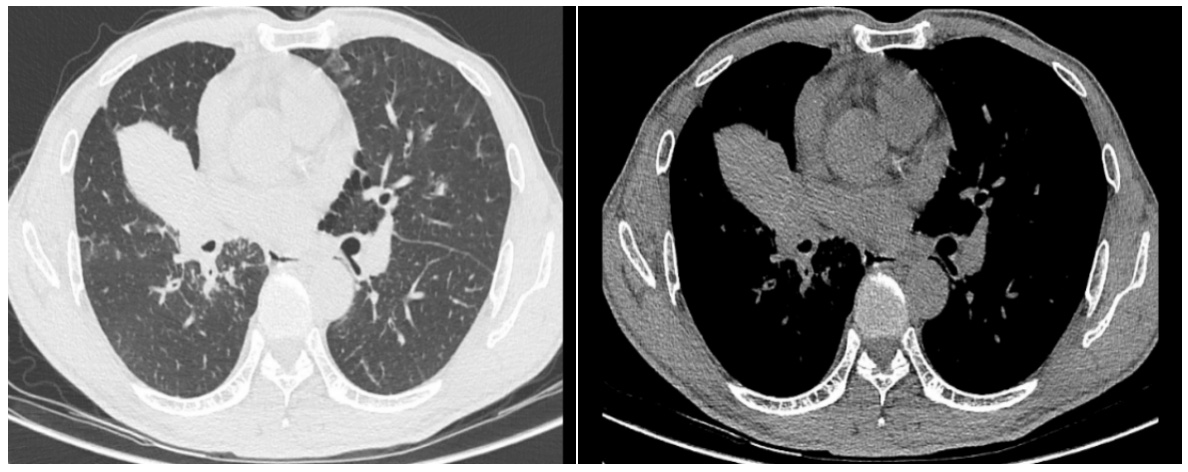

呼吸与危重症医学科罗胜主任接诊后,立即组织医疗团队对病情进行深入分析。结合刘叔的胸部影像学报告,医疗团队初步判断其存在“右肺门肺肿瘤、肺门淋巴结肿大”。罗胜主任指出:“病灶位置很深,紧贴着大血管,常规检查手段难以安全到达,诊断面临很大挑战。”

传统支气管镜受限于视野与操作范围,无法安全触及位置较深的肺门淋巴结;若采用盲目穿刺,不仅极易损伤周围血管引发大出血,还可能因取样不准确导致误诊、漏诊,诊疗风险极高。面对这一难题,医疗团队经过充分讨论,决定为刘叔实施超声小探头引导下经支气管镜肺活检术。

术中,医生将直径仅约2毫米的超声微探头经支气管镜送入气道,对目标区域进行360°实时扫描,清晰显示病灶及其周边血管关系,实现了“精准导航”。在超声实时监测下,团队成功钳取8块高质量组织标本。整个手术过程出血极少,患者术后仅轻微咳嗽,恢复良好。